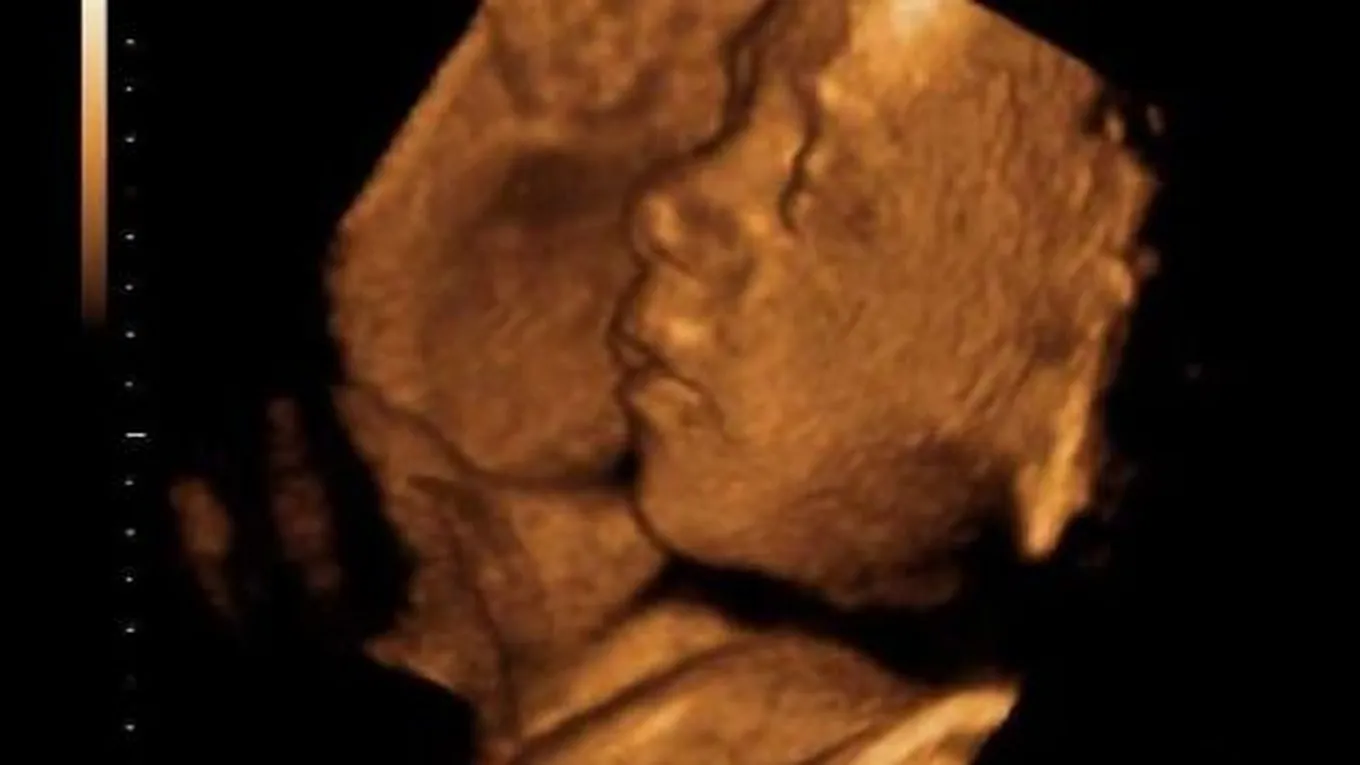

أعراض تشوه الجنين

لتشوهات الجنين أنواع لها أعراض مختلفة فمنها ما يمكن معرفته في الشهور الثلاثة الأولى، والتي تظهر عند تشكُّل أجهزة الجنين، أو أنواع تتم معرفتها بعد ستة شهور من الحمل، ومنها أيضاً ما تظهر بعد الولادة خاصة التي تكون عبارة عن تشوّهات شكلية، كما أنّ منها ما لا يُكتشف إلا بعد فترة من الولادة وهي التشوهات المتعلقة بوظائف الأعضاء، ويستطيع الطبيب معرفة أعراض تشوه الجنين عن طريق الأجهزة المتطورة وهي أجهزة السونار في الأشهر الثلاثة الأولى من الحمل.